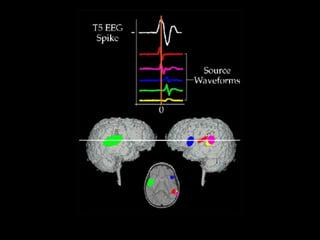

EEG y Potenciales Evocados Descripción general Desde las neuronas a cuero cabelludo Mecanismos de origen EEG, PE y neurociencia Análisis de las señales (curvas)